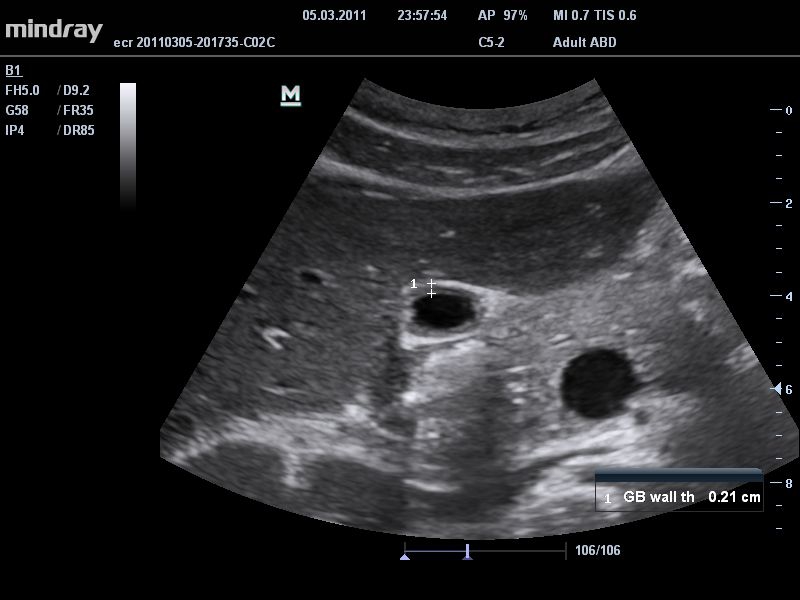

• THI со сдвигом фазы: увеличивает четкость визуализации желчного и мочевого пузыря и повышает отношение сигнал-шум.

Общая визуализация:

Да